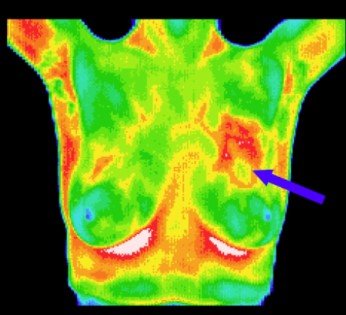

At Indianova Heart Center and Diagnostics, we offer Thermal Mammography, a non-invasive, radiation-free method for early detection of breast abnormalities. Unlike traditional mammograms, thermal imaging uses infrared technology to detect subtle heat patterns and blood flow changes that may indicate early signs of breast disease.

Thermal Mammography: Captures thermal images of breast tissue, highlighting temperature variations that can reveal potential abnormalities.

Early Detection: Identifies physiological changes even before structural changes appear.